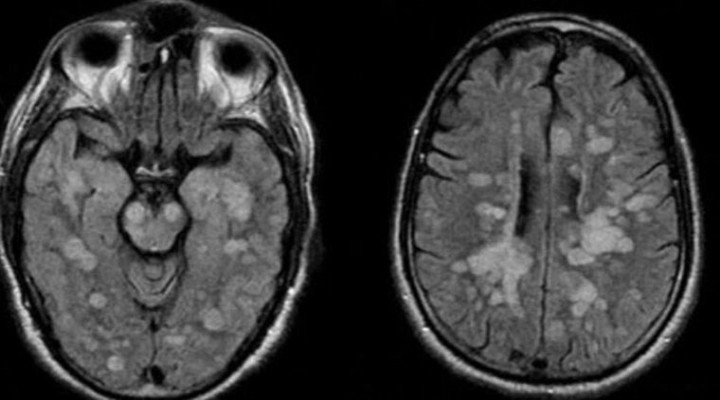

Talihsiz çocu?a vücudun ba????kl?k sistemi kendisine sald?rarak omurilik ve beynin ?i?mesine neden olan nadir bir akut yay?lm?? Ensefalit (ADEM) te?hisi koyuldu.

Braun’un Akut dissemine ensefalomyelit (ADEM) santral sinir sisteminin immun arac?l?kl? bir bozuklu?una yakaland??? bildirildi.